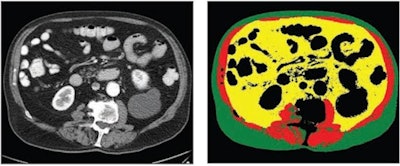

Next, the researchers utilized their previous deep-learning approach to perform fully automated analysis at the L3 vertebral level for three body composition areas: skeletal muscle area, visceral fat area, and subcutaneous fat area. Reference curves normalized by age, sex, and race were used to generate z scores for the three body composition areas. Any subsequent myocardial infarction or stroke among the participants was determined by a review of their electronic health records.